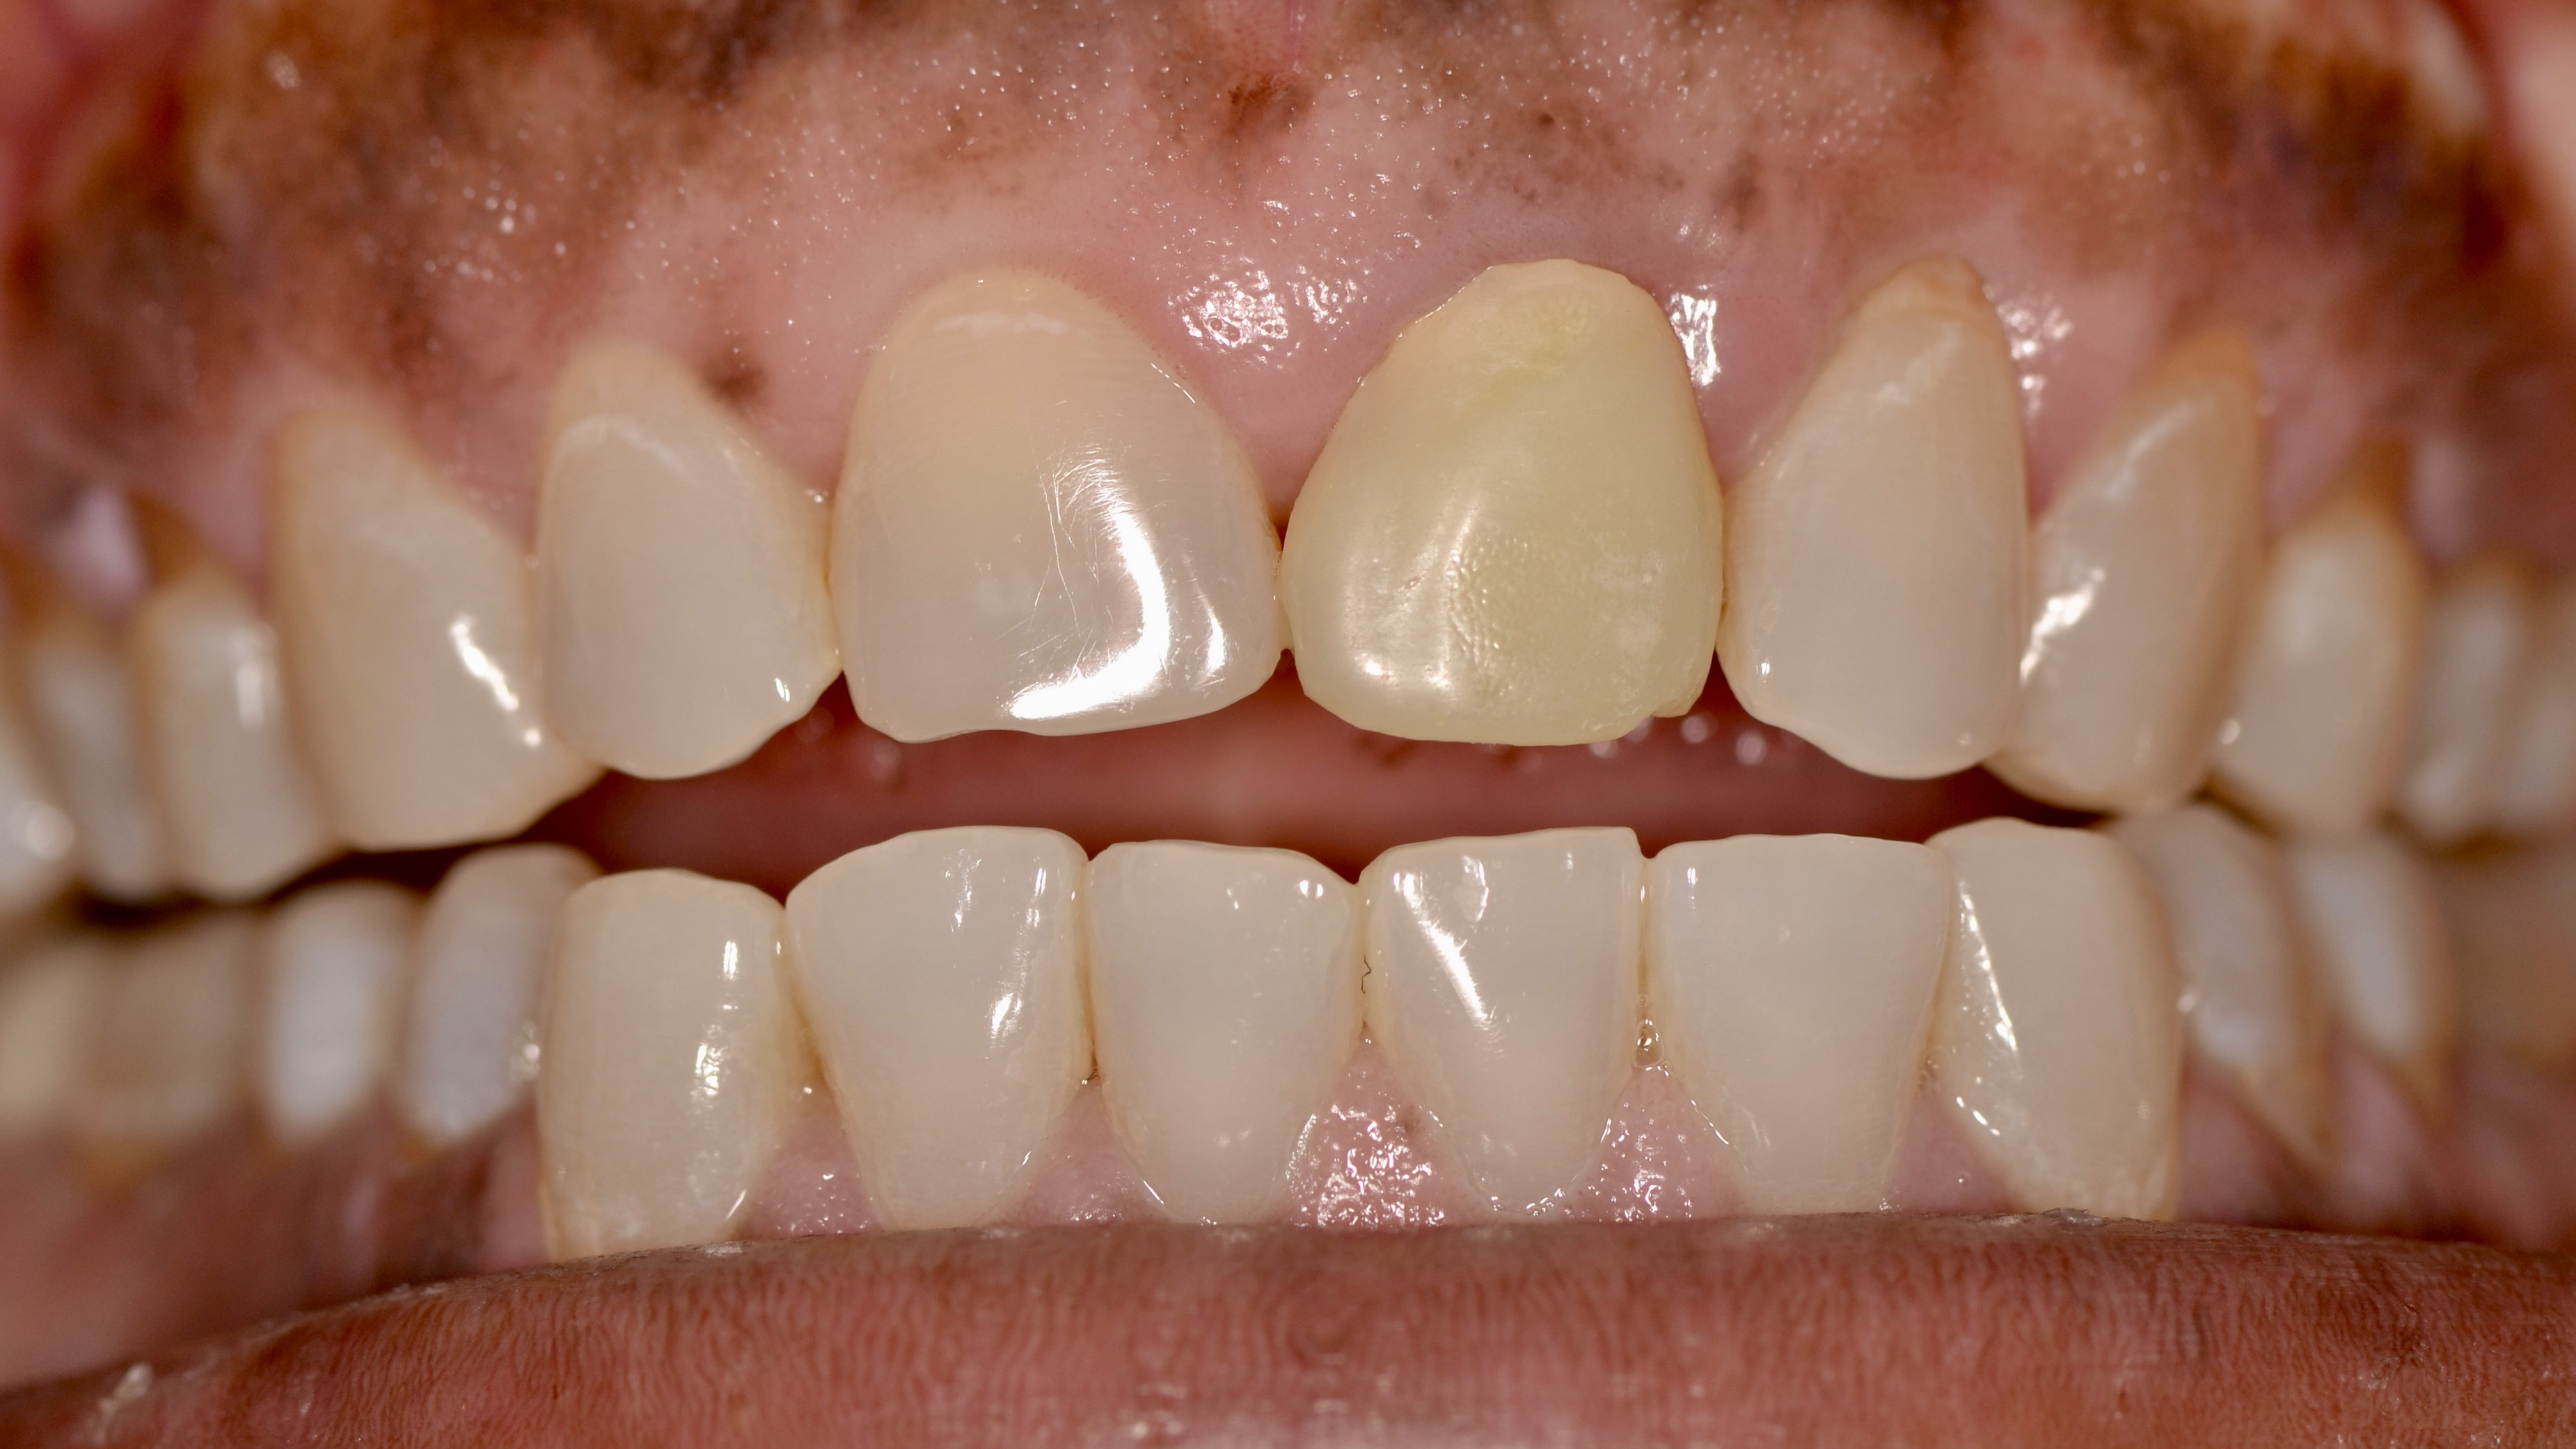

Front Tooth Trauma